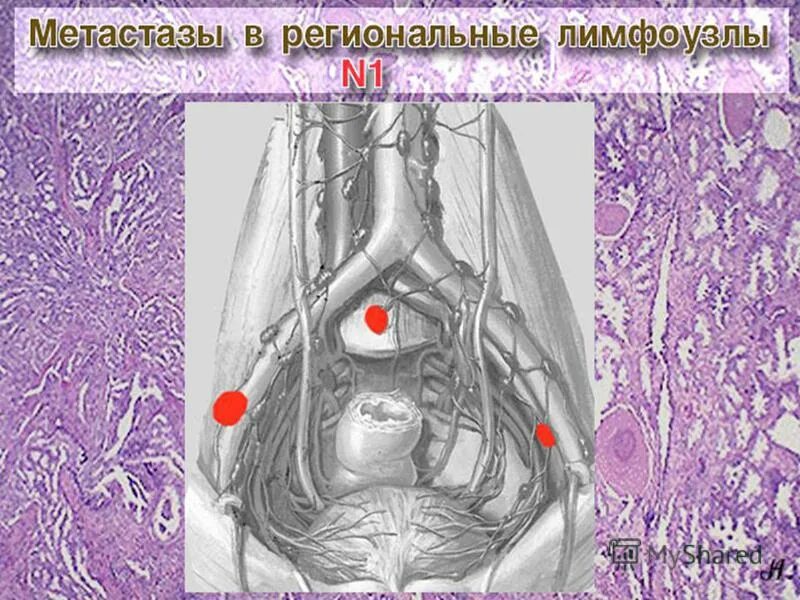

В лимфоузлах метастазы выживаемости